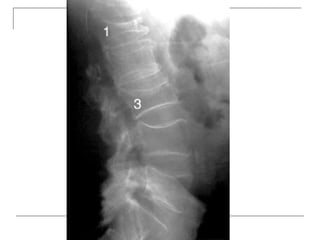

• 25.

Lateral -fracture/wedging -kyphosis -spondylolisthesis  Oblique -spondylolysis (SCOTTIE DOG)